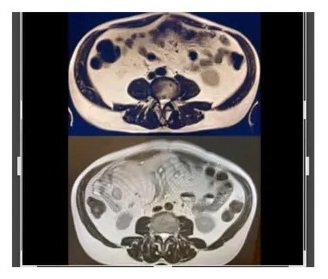

This shows just how fast Visceral Fat is eliminated by simply cutting out PROCESSED FOODS from your diet! In this case series this 68-year-old male client just eliminated processed foods and nothing else, turning from a belly bulging 68-year-old to having a waist/abdomen like a collegiate athlete in their twenties. He did NOT exercise ONE MINUTE. Honestly, you are likely wasting your precious time exercising if you are continuing to eat processed foods. I scan clients to show what really matters - their visceral fat! After showing them their own visceral fat, I provide every client with over 40 strategies to eliminate it and with it their chronic disease.

3. Heart Fat is Eliminated When Visceral Fat is Eliminated

The MRI scan on the left shows a large amount of pericardial fat in the same 68-year-old business executive and how much it was reduced (right side of image). This client experienced this result in just 13 weeks from simply eliminating processed foods and again without exercising one minute, providing evidence that diet matters the most. How much fat do you have around your heart? Pericardial fat almost always correlates with visceral fat. When one is eliminated the other improves.